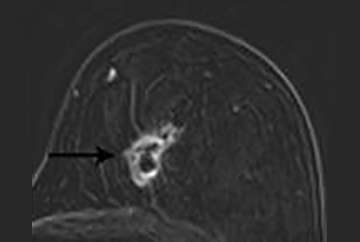

A new enhancing mass (Figure 5), especially those with irregular or spiculated margins, are highly suspicious (BI-RADS 4 or 5).

FIGURE 5: T1-weighted post contrast image with fat saturation. A new mass with irregular margins at a lumpectomy site. Biopsy demonstrated recurrent breast cancer.